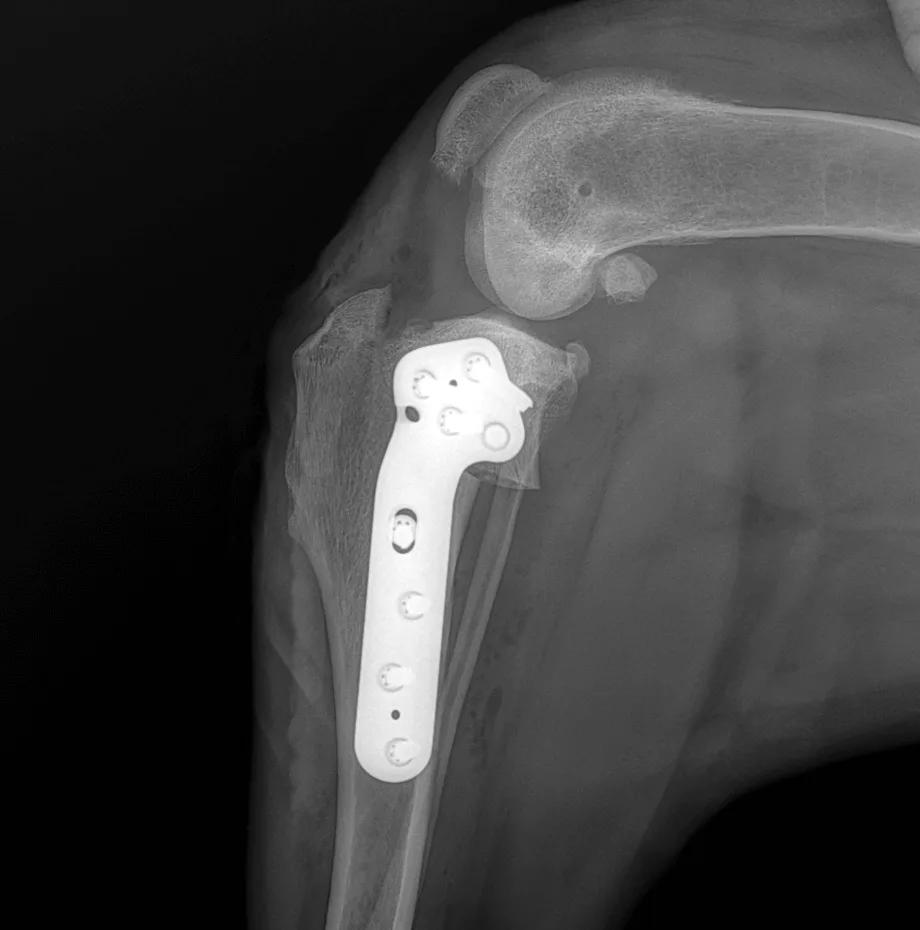

Radiographie postopératoire de la technique TPLO. On voit le plateau tibial pivoté, qui est fixé à l'aide d'une plaque spéciale.

TPLO, Tibial Plateau Leveling Osteotomy

L’inclinaison du plateau tibial est modifiée chirurgicalement afin de changer l’axe de charge du genou. La fonction stabilisatrice du ligament croisé antérieur est ainsi neutralisée sans devoir le remplacer. Au vu du nombre croissant d’études objectives, la TPLO est la seule méthode ayant montré un niveau de charge comparable à celui du membre sain. Elle est considérée comme le standard d’or international de la chirurgie du ligament croisé chez le chien et convient aux chiens de toutes tailles.